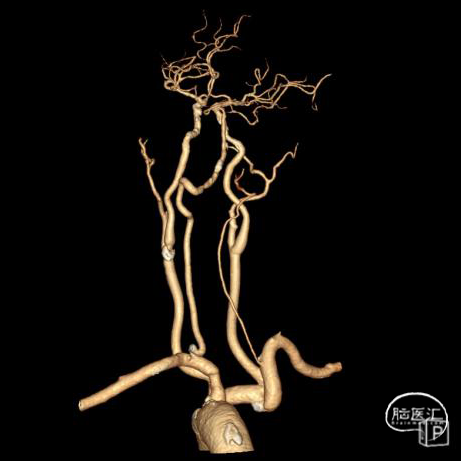

➢头颈部CTA(三维重建MIP像)

➢头颈部CTA(原始像)

该患者术前影像学提示右椎纤细、V4段未汇入基底动脉,考虑孤立椎。且左椎开口存在重度狭窄,左椎V4存在局部重度狭窄可能,故该患者存在血管内介入治疗指征,排除禁忌症后拟行“全脑血管造影术+左侧椎动脉开口血管成形术”。

➢术后定期随访情况

术前影像考虑右侧孤立椎,左侧椎动脉V1段重度狭窄、狭窄段以远扭曲成襻且合并长节段多发动脉粥样硬化狭窄改变(夹层待排),同时左椎V4段局部重度狭窄可能;

术中造影证实右椎纤细、右椎V4段可见微弱血流入基底动脉、左椎动脉开口闭塞、颈升动脉通过侧支循环向左椎V3供血并逆流至V1中段、左椎V4轻度狭窄;